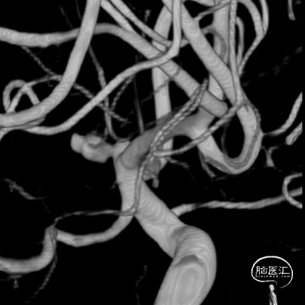

气管插管全麻后全脑血管造影示:

右侧颈内动脉-前交通起始段动脉瘤,动脉瘤大小约3.8*2.5mm,瘤颈约1.0mm,动脉瘤起源于右侧大脑前A1段后壁,朝向后内上,考虑为责任动脉瘤,根据动脉瘤大小、形态等,拟行单纯弹簧圈栓塞治疗。